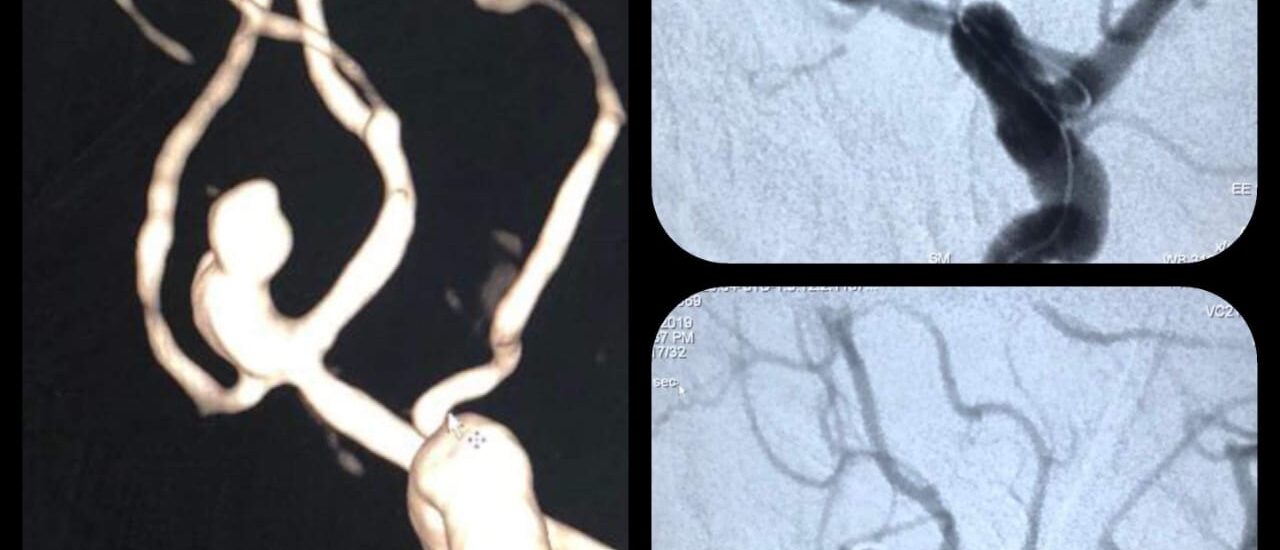

Correction of Congenital sharp angular kyphosis

Female pt 14 yrs, complaining from back pain due to congenital sharp angular kyphosis otherwise there wasn’t any neurological deficit Pre-op X-ray 3D Reconstruction Surgical planing for vertebral column resection of the apical vertebra using surgimap program for accurate correction according to Sagittal balance parameters…